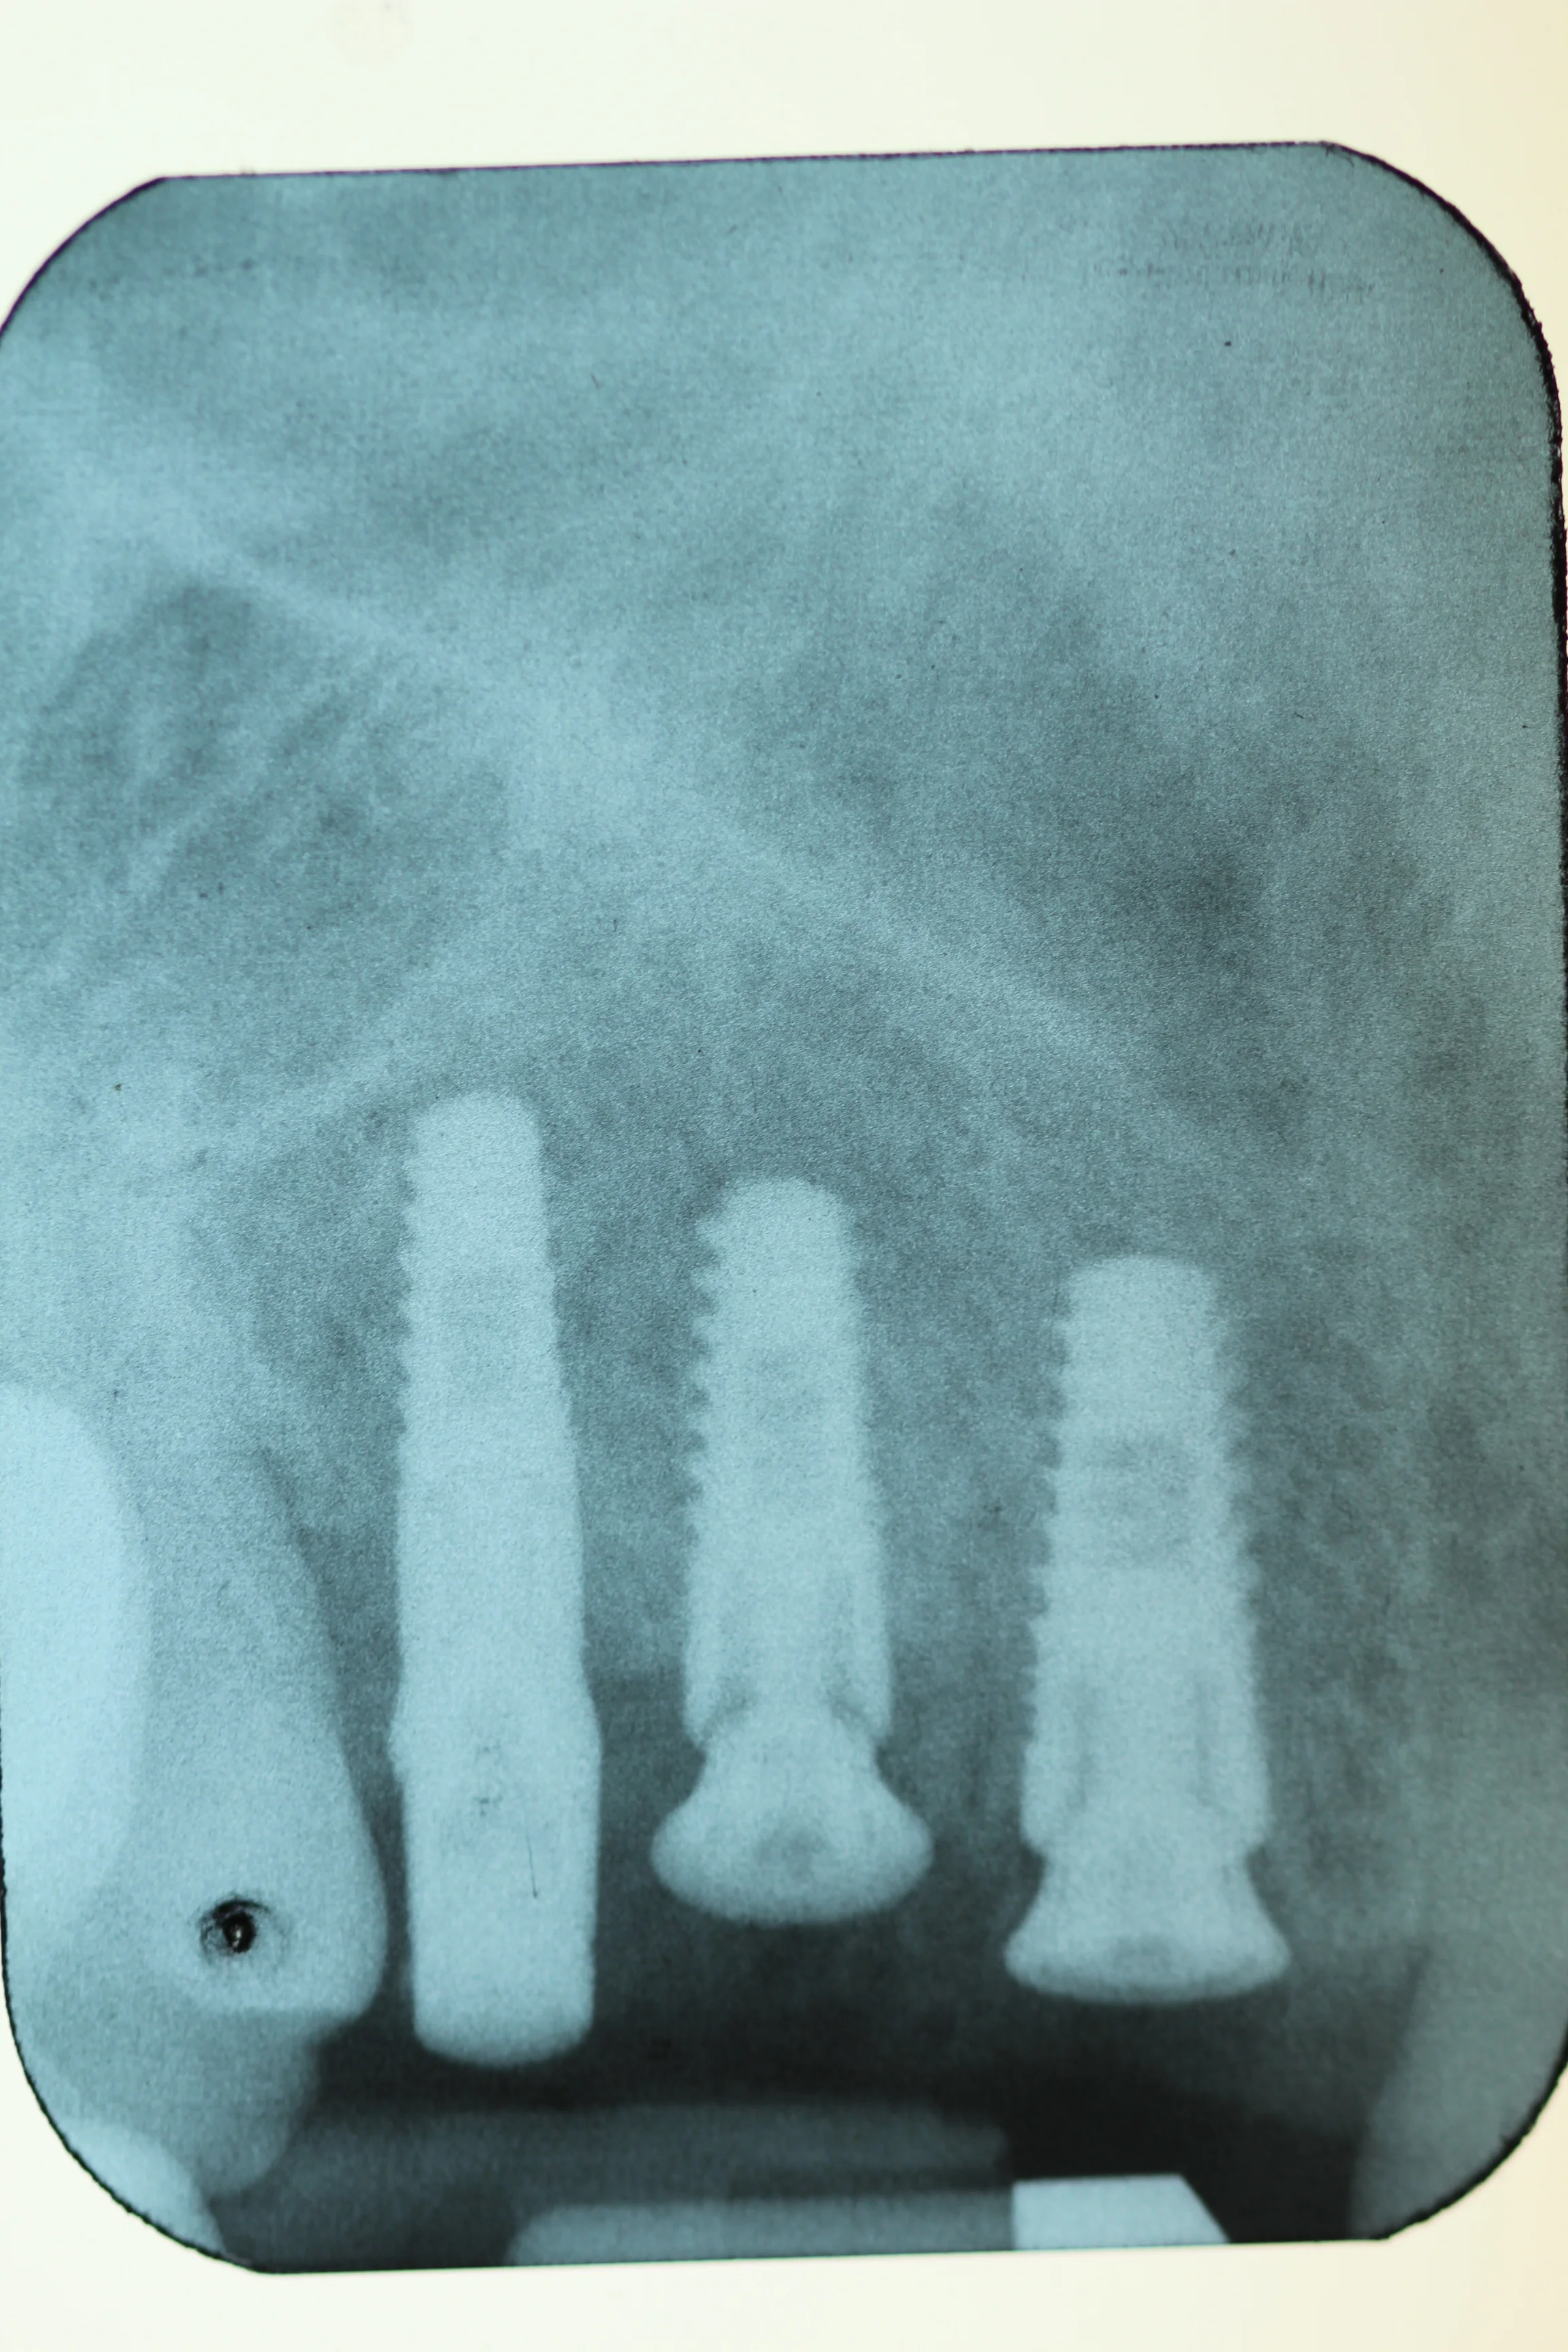

Once the implantologist is happy they will often place a direction indicator in the pre-made hole this is just to assess what direction that the implant will be. They may also take x-rays with drill pieces in the hole as they are going along this is to make sure that everything is going as best it can and so that they can measure accurately.

Implant Procedure Step 1 - Investigation

The initial stage for having an implant done is the investigation. This stage is where the implantologist will go through options with you, take x-rays and photographs and start to plan exactly where the implants will be placed.

During this stage sometimes the implantologist will request that you have a 'surgical guide' made. This is like a denture that is clear and has holes drilled into it. This assists the implantologist when placing the implants to improve accuracy.

They may also request that you have a CBCT scan done. This allows them to use special programs on their computers to plan and place implants. This means that they have an even better idea of the best place to insert the implant to ensure the highest success rate.